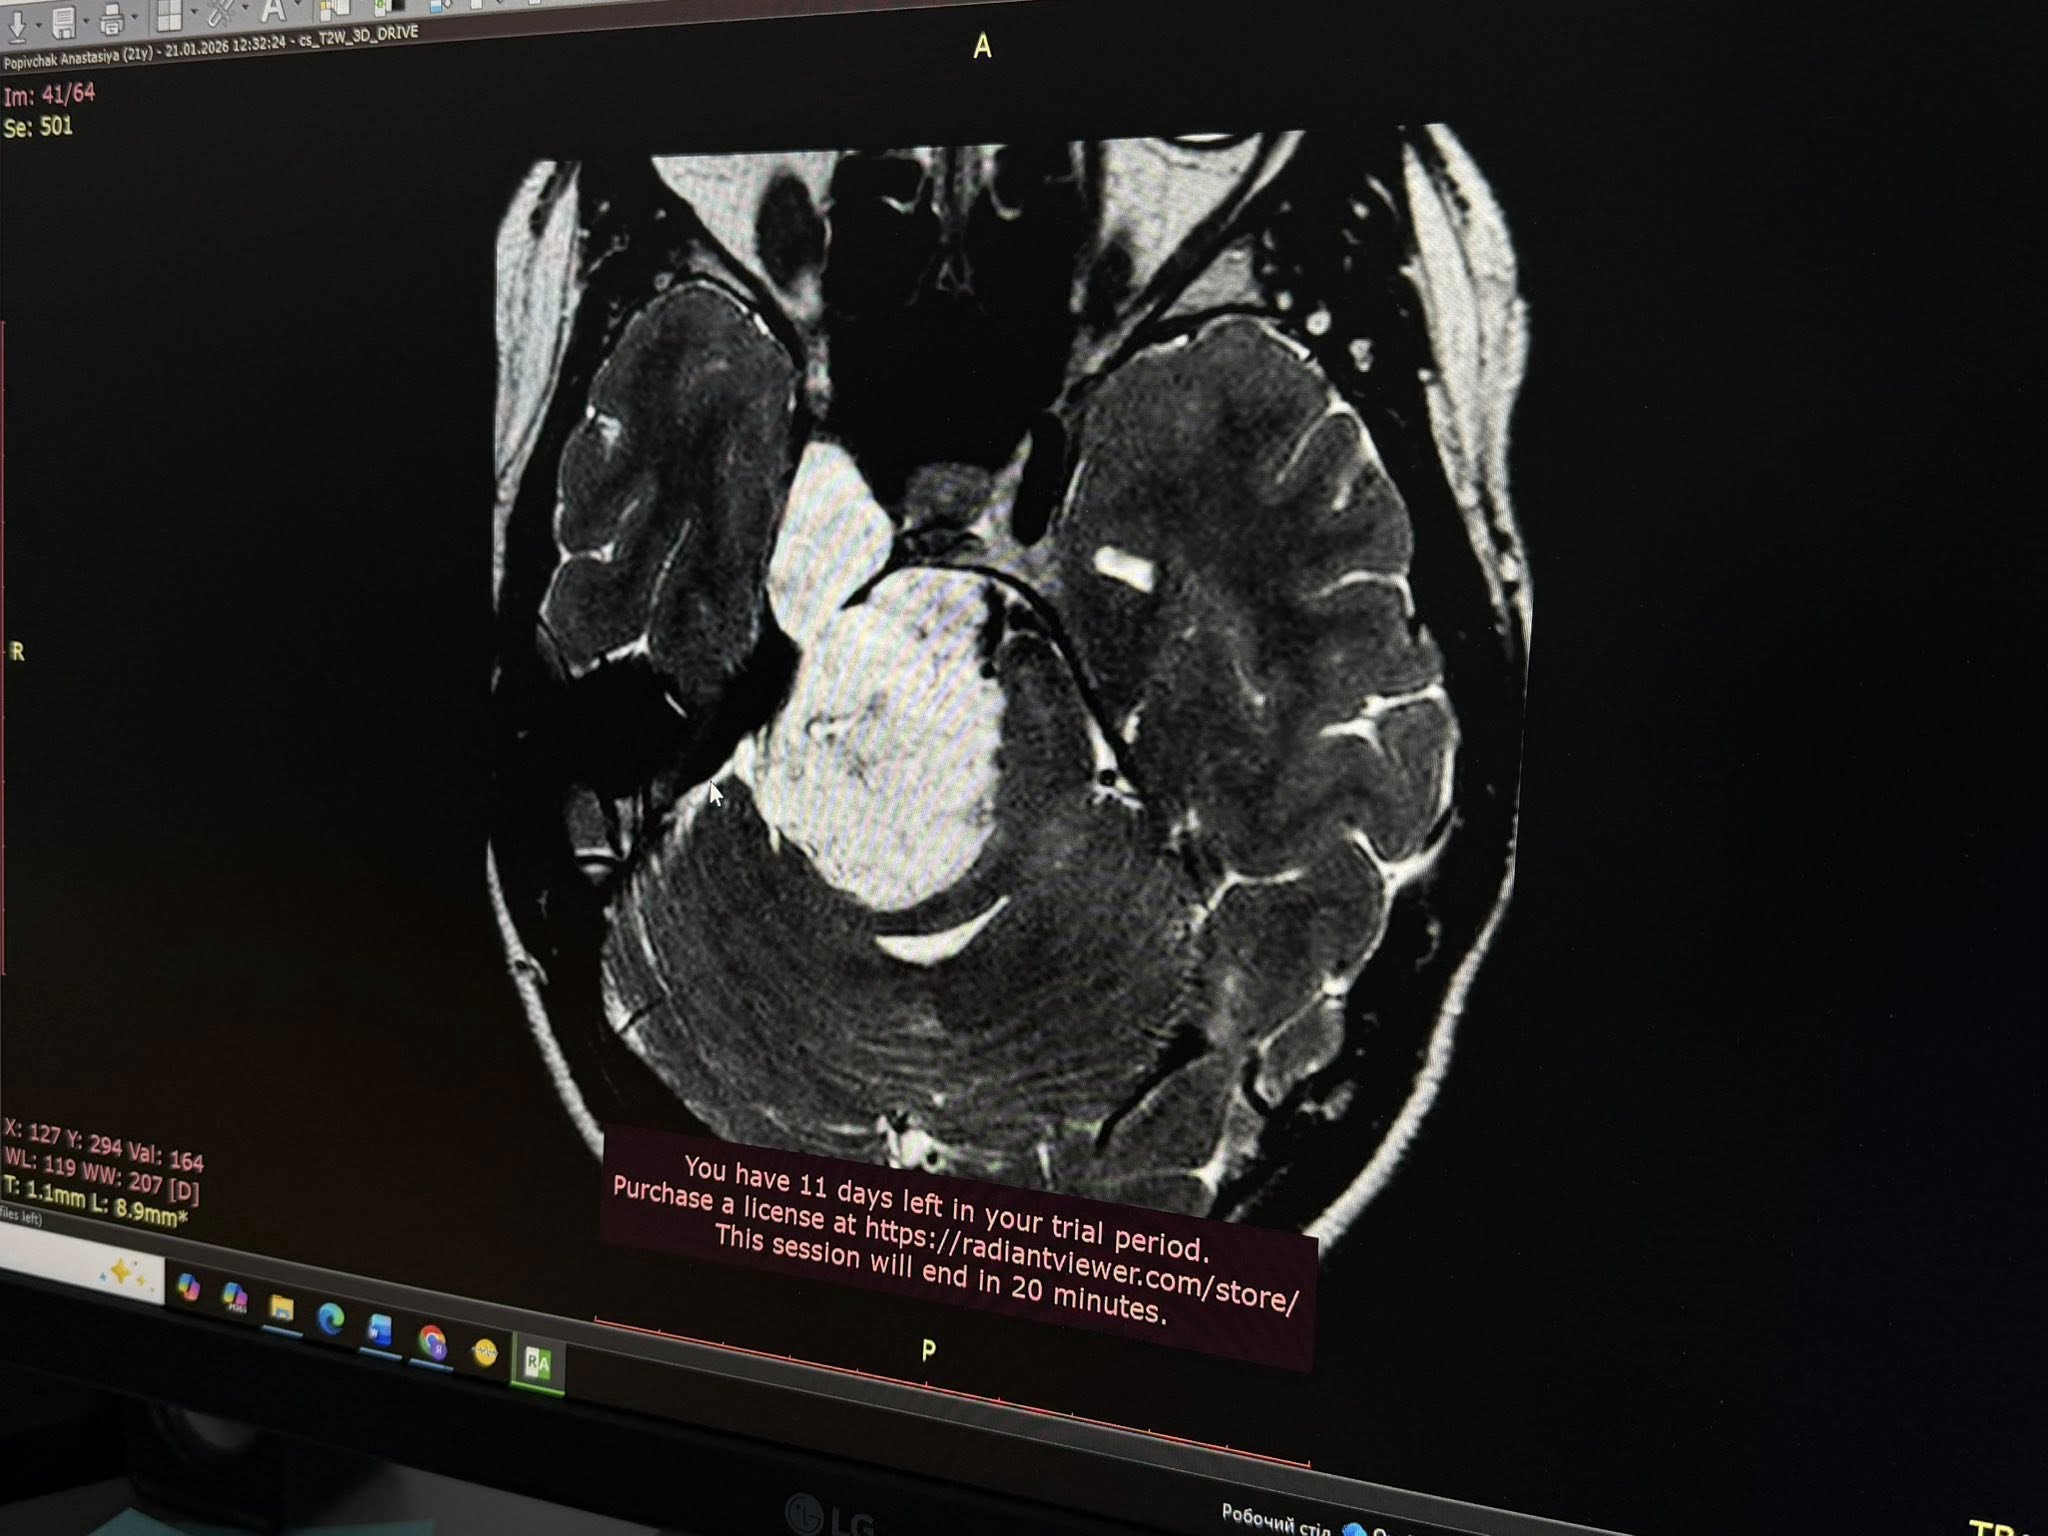

«Я була в шоці. Це було дуже неочікувано. Я розглядала різні варіанти, але не такий. Проте рук не опустила, зрозуміла, що потрібно шукати вихід і лікарів, яким можна довіритися», — згадує Анастасія.Довірилася своїм – львівським нейрохірургам Лікарні Святого Пантелеймона, а ті своєю чергою зіткнулися з доволі рідкісним випадком розташування пухлини. Виявилося, що у мозку Анастасії розросталася холестеатома – доброякісне новоутворення, яке зазвичай виникає у середньому вусі. Натомість у цієї пацієнтки пухлина поширилася на дві з трьох черепних ямок: на задню та середню, що є вкрай нетиповим та небезпечним.

Холестеатома виросла до загрозливих розмірів – 6 на 3 сантиметри – та вже стискала стовбур мозку, що й пояснювало проблеми зі слухом, зором та координацією. Ба більше – в задній черепній ямці також розташовані і центри дихання та серцевої діяльності, а це вже становило пряму небезпеку для життя Анастасії. Вона просто могла перестати дихати. Треба було якомога скоріше видалити пухлину, однак її локалізація значно ускладнювала цю задачу, зазначають медики.